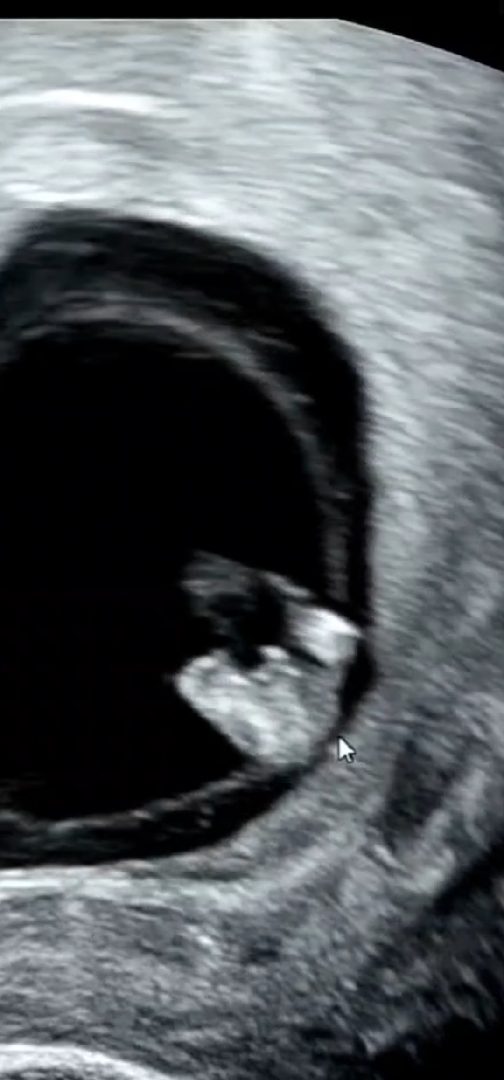

9주초음파인데... 삼각점이라는걸 이번에 처음 알아서 혹시나해서 돌려보니까 삼각점이 보이는거 같은뎈ㅋㅋㄱㄱ 9주에도 삼각점이 보이나요?😅 남아일까요?